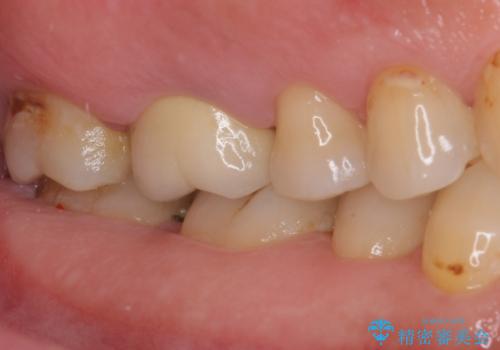

歯周外科処置を併用した奥歯の補綴治療

- クラウンが装着された奥歯から、歯磨きの度に出血するとのことで来院された患者様です。

虫歯が歯肉の奥深くにまで及んでおり、歯肉が腫れやすい状態となっていたため、歯肉の切除並びに歯槽骨の形態修正を行い、虫歯が歯肉の外に出てくるようにした上で、オールセラミックにて補綴することとしました。

歯間ブラシを通す度に出血をするのは、ご自身の磨き方が悪いからと思っていらっしゃいましたが、治療後は全く出血することがなくなり、患者様には大変満足していただきました。